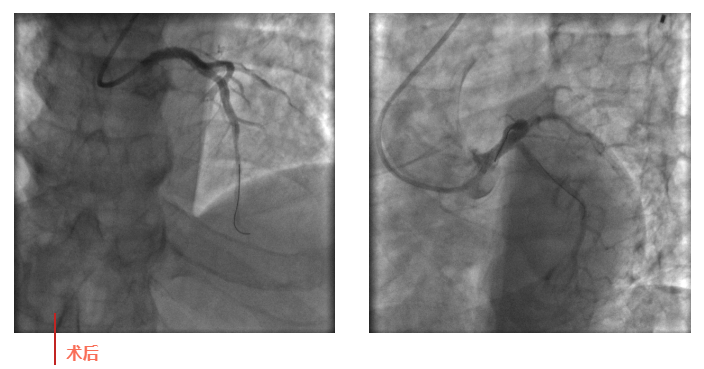

心血管內(nèi)科副主任徐先進(jìn)在主任助理農(nóng)彥林和主任汪念東的配合下行冠狀動(dòng)脈造影,結(jié)果如術(shù)前判斷一致,左主干重度狹窄,患者命懸一線。對(duì)團(tuán)隊(duì)緊急處置非常信任的李阿姨,毫無疑慮地聽取了術(shù)者的建議,同意在血管內(nèi)超聲(IVUS)的精準(zhǔn)指導(dǎo)下,在患者左主干內(nèi)植入一枚支架,成功拯救了患者的生命。

術(shù)后,患者轉(zhuǎn)入心血管內(nèi)科CCU病房,在IABP泵的支持下渡過了危險(xiǎn)期。李阿姨紅著眼眶坐在床邊,仍心有余悸,“還好有你們?。≌媸翘x謝了!”經(jīng)過心血管內(nèi)科團(tuán)隊(duì)的精心治療和護(hù)理,患者現(xiàn)已康復(fù)出院。